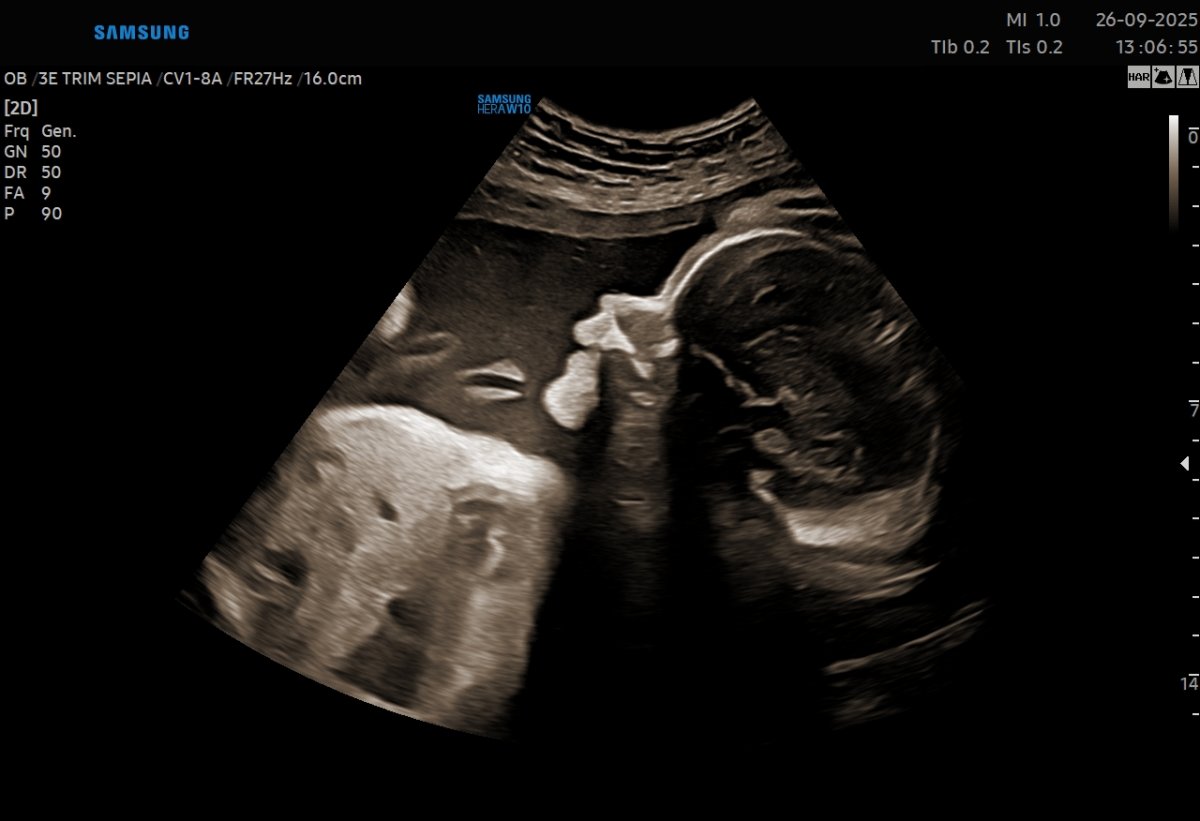

Gallerie de photos